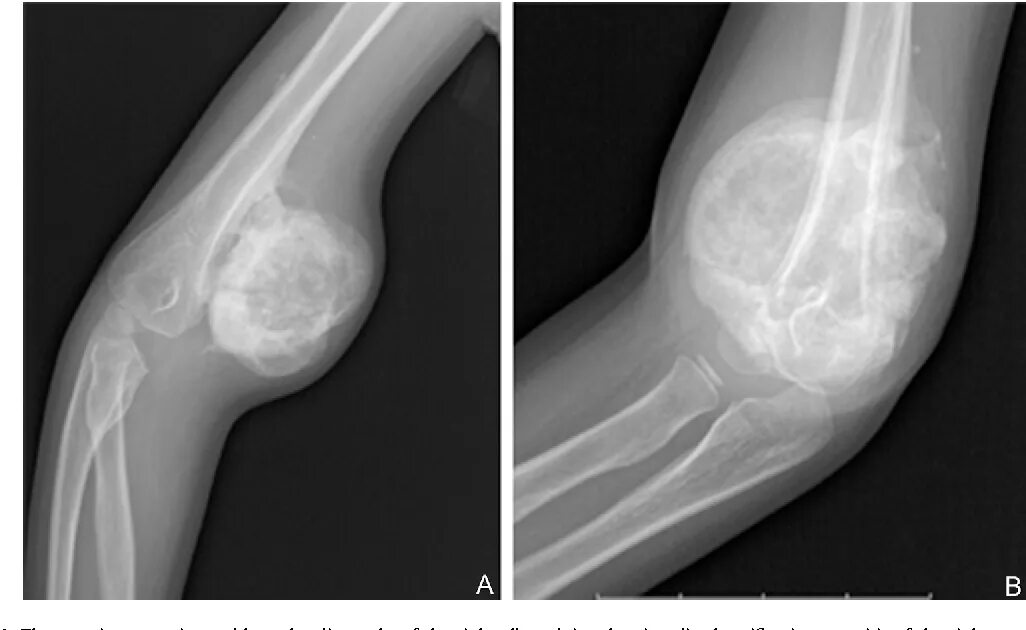

Оссифицированный миозит